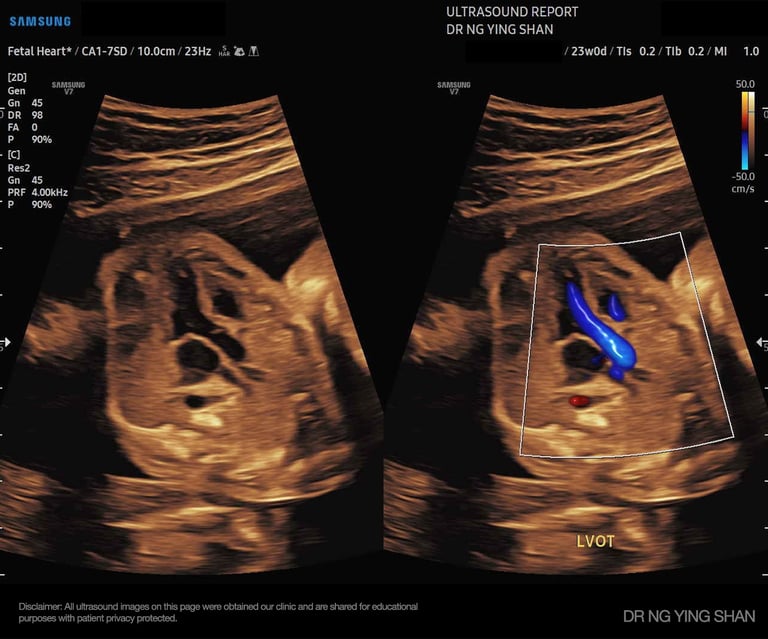

Detailed / Anomaly Scan

Looks closely at the baby’s organs, spine, heart, limbs, placenta, and amniotic fluid to check that everything is developing well.